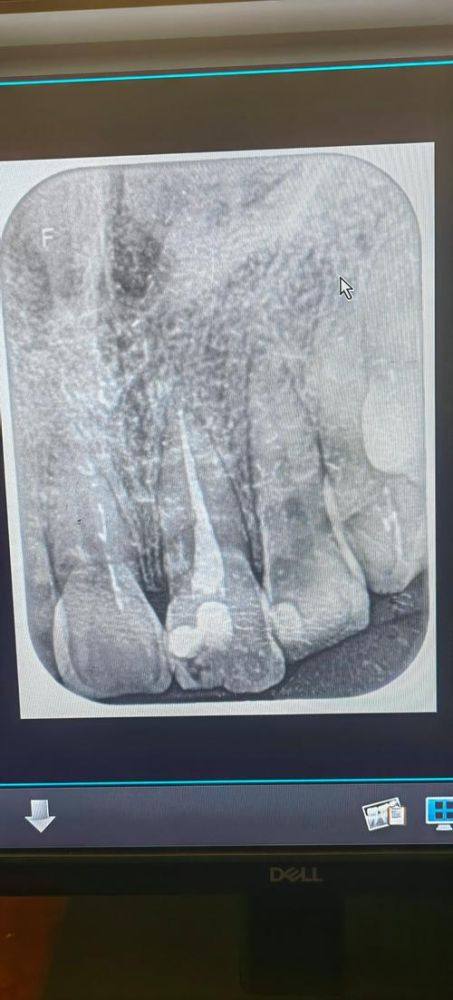

山东德州夏津董传兴口腔拥有经验多的医护团队,能够根据患者个体情况定制个性化治疗方案,配备数字化牙科影像设备、全景X光机、激光治疗仪等精良诊疗仪器,保护诊断与治疗的精细性。诊所环境舒适温馨,就医体验良好,收费亲民合理,无隐形消费,秉承以患者为中 心的服务理念,注重与患者沟通,缓解患者就医焦虑,收获了当地患者“服务周到、技术娴熟”的良好口碑,是夏津本地高人气的口腔医疗机构。

口腔内科:可开展补牙、根管治疗等常见口腔内科诊疗,解决各类牙体牙髓问题

根管治疗:精细处理牙髓感染问题,较大程度保留患牙